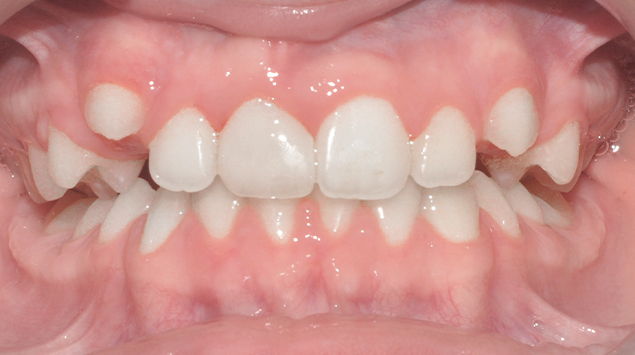

>   Zdjęcie po leczeniu.

>   Zdjęcia pokazują pacjentkę przed i po zabiegu autotransplantacji, a także zmiany w położeniu tkanek miękkich. Po przeprowadzeniu zabiegu, który miał na celu uzupełnienie brakującego zęba siecznego lewego. Osiągnięte zostało poszerzenie i uwypuklenie się okolicy podnosowej.